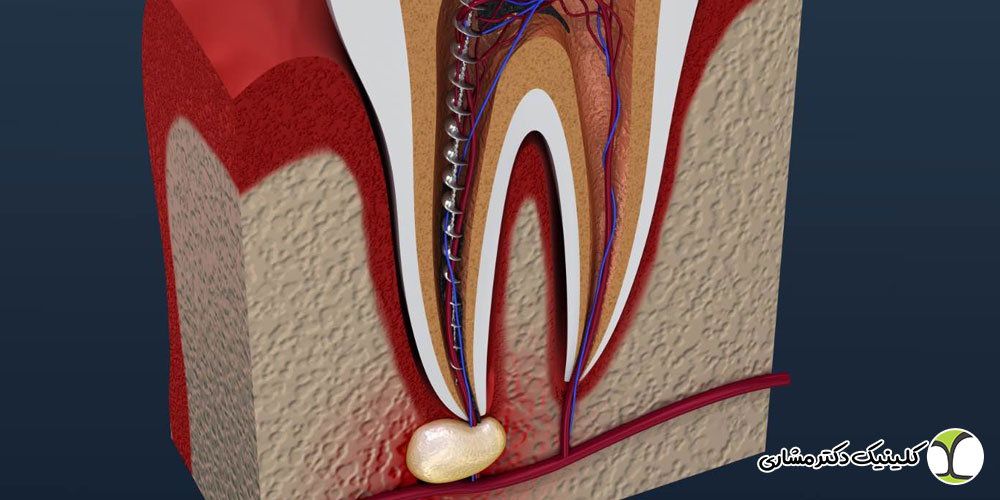

گوشت دندان (پالپ) شامل عصب، رگهای خونی و بافت های زنده است. زمانی که این بخش دچار التهاب، عفونت یا آسیب جدی میشود، بیمار علائم مشخصی را تجربه میکند. اگر این علائم نادیده گرفته شوند، درمان ممکن است پیچیده تر شود و حتی منجر به از دست رفتن دندان گردد.

تورم، آبسه و نرمی لثه در نزدیکی دندان

وجود یک تورم یا برآمدگی کوچک روی لثه که گاهی شبیه جوش است، یکی از نشانه های قطعی عفونت ریشه دندان است. این برجستگی که به آن فیستول یا سینوس تراکت گفته میشود، ممکن است همراه با:

- خروج چرک

- مزه تلخ و ناخوشایند

- بوی بد دهان

- درد ضربهای یا فشار در ناحیه دندان

باشد. تورم به معنای تجمع چرک در اطراف ریشه است و نشان میدهد عفونت از پالپ دندان عبور کرده و به استخوان فک رسیده است. در این مرحله درمان ریشه باید هرچه سریع تر انجام شود تا از تخریب استخوان جلوگیری گردد.

نادیده گرفتن علائم پوسیدگی عمیق یا عفونت دندان میتواند عواقب جدی و برگشت ناپذیری به همراه داشته باشد. زمانی که پالپ دندان دچار التهاب یا عفونت میشود، با پیشروی بیماری، باکتریها به ریشه و سپس به استخوان اطراف گسترش مییابند. این روند میتواند باعث تشکیل آبسههای بسیار دردناک، تورم شدید و حتی تخریب استخوان فک شود.

در صورتی که درمان ریشه به موقع انجام نشود، دندان معمولاً دیگر قابل حفظ نیست و چارهای جز کشیدن دندان باقی نمیماند. علاوه بر این، عفونت درمان نشده ممکن است به بافتهای اطراف، سینوسها و حتی جریان خون منتشر شود و مشکلات جدی تری برای سلامت عمومی ایجاد کند.